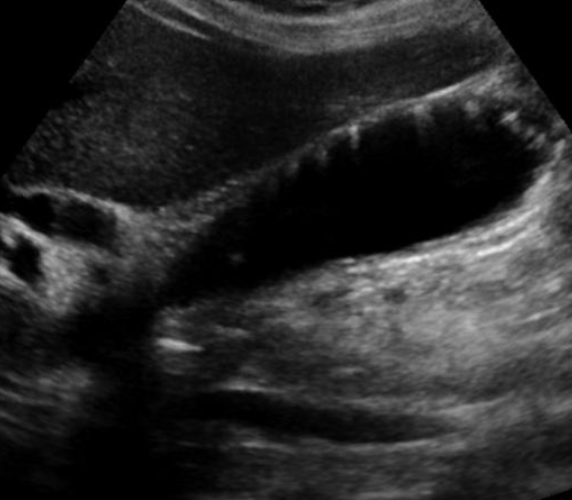

What is this?

Adenomyomatosis

- most comon form of hyperplastic cholesterolosis

- marked hyperplasia of the GB wall

- Epithelium herniates into the wall

- forms rokitansky-Aschoff sinuses

- May be focal or diffuse

- IMAGING FINDINGS

- Rokitansky-Ashkoff sinues

- hypoechoic if contain bile

- hyperechoic if contain sludge or calculi

- High amplitude foic in the wall (cholesterol crystals) that produce comet tail artifacts (V shpaed ring down artifacts)

- Thickening of GB wall is common but non specific

- inflammation is not typical

- hypercontractility

- Rokitansky-Ashkoff sinues

- MRI

- Rokitansky-aschoff sinuses

- T1 hypo

- T2 hyper

- non enhancing

- Thickening of GB wall Nonspecific

- Inflammation is not typical

- Rokitansky-aschoff sinuses